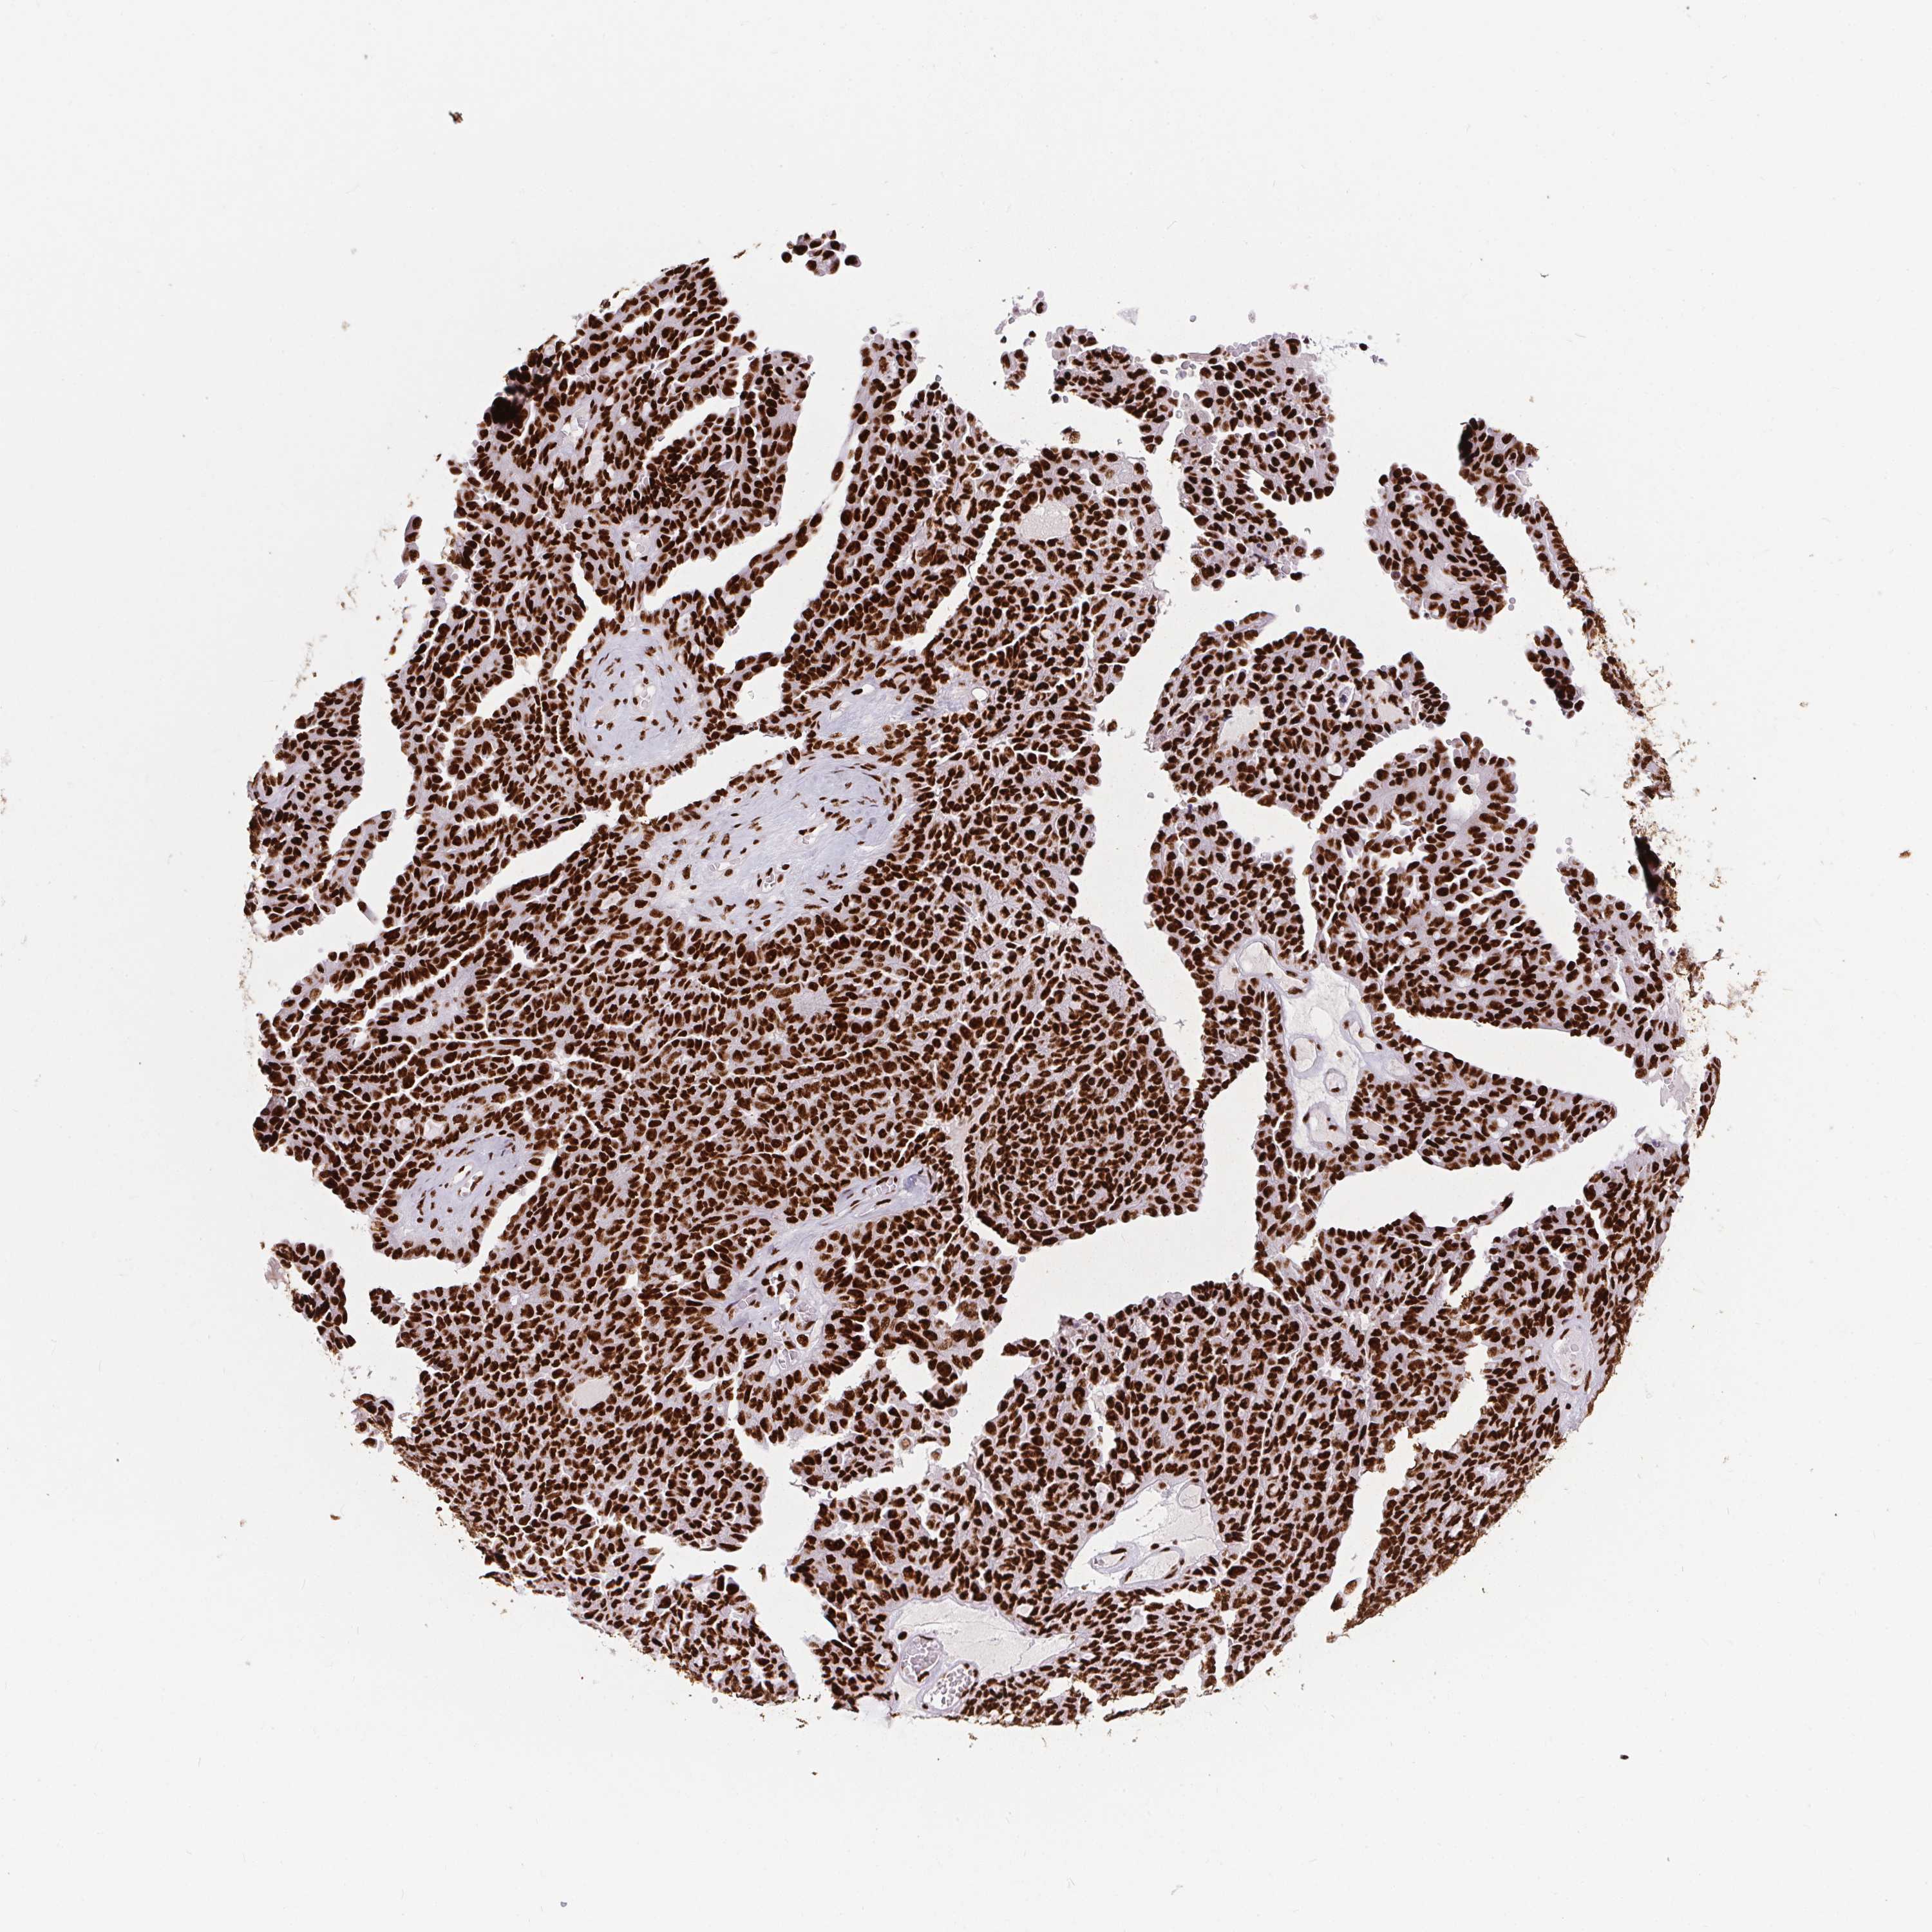

OVARIAN CANCER - Protein expressioni

A mouse-over function shows sample information and annotation data. Click on an image to view it in a full screen mode. Samples can be filtered based on level of antibody staining by selecting one or several of the following categories: high, medium, low and not detected. The assay and annotation is described here.

Note that samples used for immunohistochemistry by the Human Protein Atlas do not correspond to samples in the TCGA dataset.

Antibody stainingi

Antibody staining in the annotated cell types in the current human tissue is reported as not detected, low, medium, or high, based on conventional immunohistochemistry profiling in selected tissues. This score is based on the combination of the staining intensity and fraction of stained cells.

Each image is clickable and will lead to virtual microscopy that enables deeper exploration of all samples and also displays staining intensity scores, fraction scores and subcellular localization as well as patient and tissue information for each sample.

Antibody HPA062248

Staining

High

Medium

Low

Not detected

Intensity

Strong

Moderate

Weak

Negative

Quantity

>75%

75%-25%

<25%

None

Location

Nuclear

Cytoplasmic/membranous

Cytoplasmic/membranous,nuclear

Cystadenocarcinoma, serous, NOS

Cystadenocarcinoma, mucinous, NOS

Carcinoma, endometroid